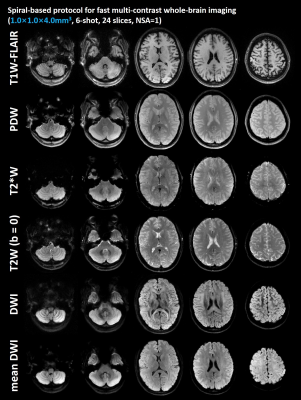

Figure 2 shows the T1W-FLAIR, T2W, PDW, T2*W, DW images with the same resolution acquired by the 6-shot spiral acquisitions from Experiment 1. Five slices are shown here. The in vivo results of the proposed protocol demonstrate satisfactory image quality, proper tissue contrast, and high spatial resolution.

Figure 2: T1W-FLAIR, T2W, PDW, T2*W, b=1000 s/mm2 DW images with an in-plane resolution of 1.0 mm2 acquired by the 6-shot spiral acquisitions. Five slices are shown here. The in vivo results of the proposed protocol demonstrate satisfactory image quality, proper tissue contrast, and high spatial resolution.